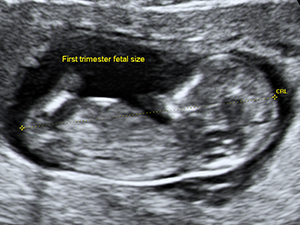

First Trimester

The crown-rump length of the fetus at 12 weeks